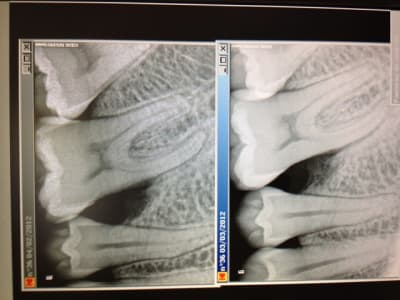

Je poste un autre cas de parodontite agressive (bilan long cone prescris) .

Entre les deux radios ,un mois s'est écoulé, une antiobiothérapie et un traitement étiologique avec surfaçage avec irrigation ont été effectués .

Une deuxième séance de surfaçage est prévue .

Des conseils ? Quand passer à la chirurgie ? Au bout de combien de temps peut on avoir une guérison complète du site ?